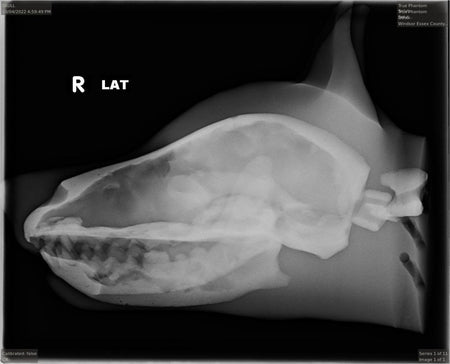

- Anatomically correct realistic skull phantom with the jaw bone

- Realistic brain tissue